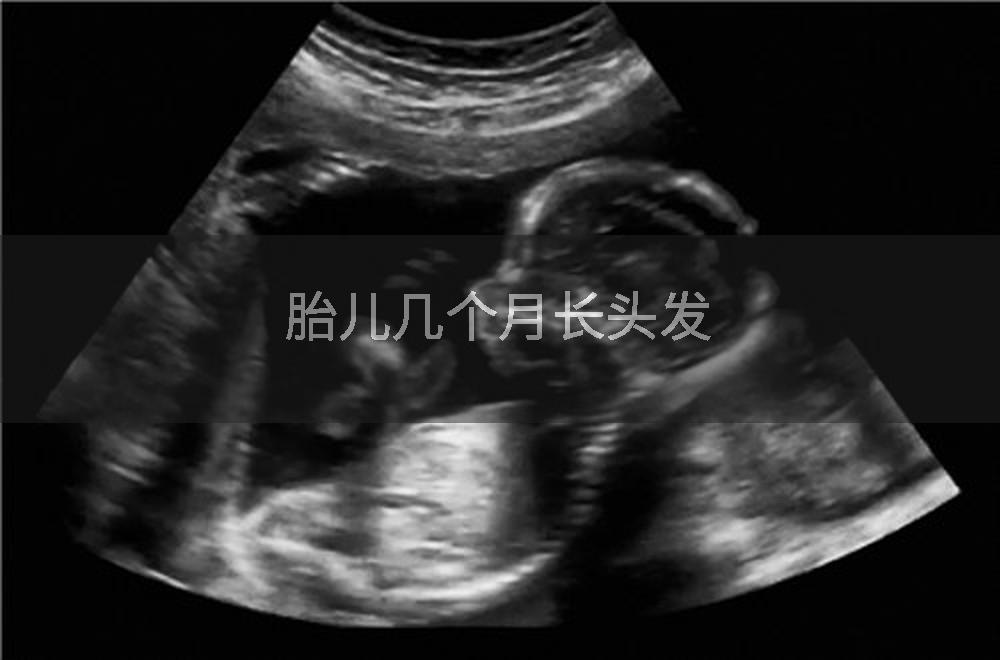

胎儿一般在怀孕第四个月开始长头发。这是因为胎儿的毛囊在怀孕早期就已经形成,但直到第四个月,胎儿的头皮上才会出现细小的毛发,即胎毛。胎毛的生长速度和数量因个体差异而异,有的胎儿可能在第五个月或更晚些时候才开始长头发。